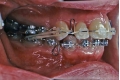

| マルチブラケット終了時

| 治療後2年経過時